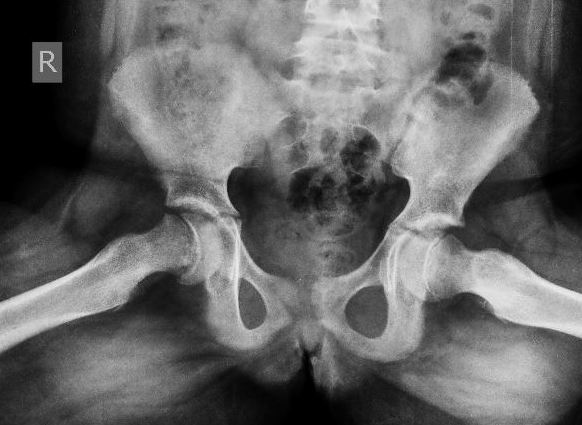

BEFORE FIXATION

SCFE can sometimes affect both hips, and boys are affected more often than girls. It can occur suddenly following an injury (acute slip) or occur over an extended period of time (chronic slip). SCFE develops most often during short periods of accelerated growth following the onset of puberty 10-16 years).

Diagnosis of SCFE